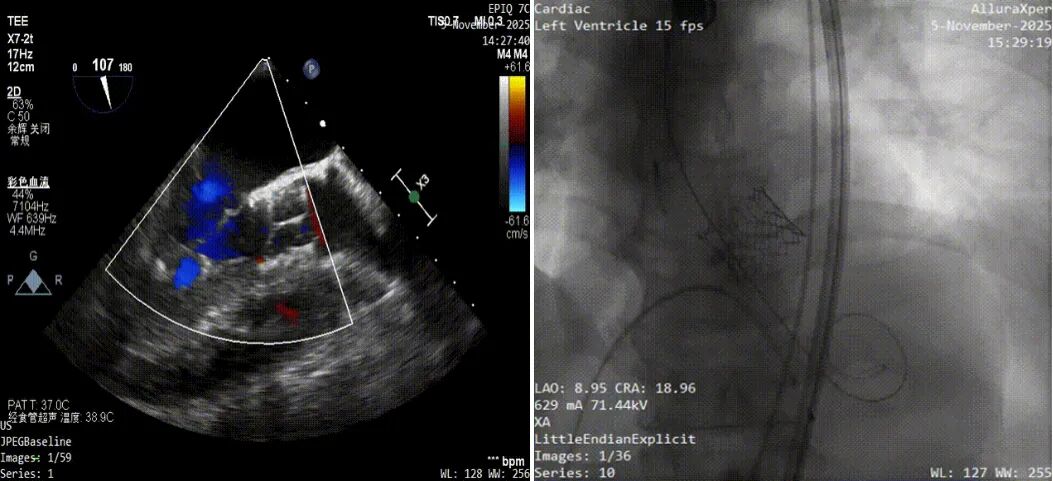

“老人年纪大,基础病多,要是做传统开胸手术,风险太高了。”心血管内科三病区张涛主任团队反复研究,最终决定采用经导管主动脉瓣置换术(TAVR)——不用开胸,通过血管就能把新瓣膜送进心脏。为了确保手术万无一失,团队提前用CT、食道超声等“精密仪器”给老人的心脏做了“全身扫描”:测算瓣膜大小、评估血管通路、确认冠脉位置,甚至模拟了新瓣膜的植入位置。

手术当天,医生先从老人右侧股动脉穿刺,打通一条通往心脏的“通道”,将装载着SAPIEN 3瓣膜精准地送达心脏瓣膜位置,让新瓣膜牢牢“扎根”,术后检查结果新瓣膜形态完美,心脏内的血流压差明显下降,原本“沉重”的心脏,终于又能轻松跳动了。手术非常成功,仅仅用了1个多小时。患者第二天就能在床上坐起来,喝粥了。术后患者也没有再发生晕厥,那个导致他晕倒的“定时炸弹”被彻底拆除了。